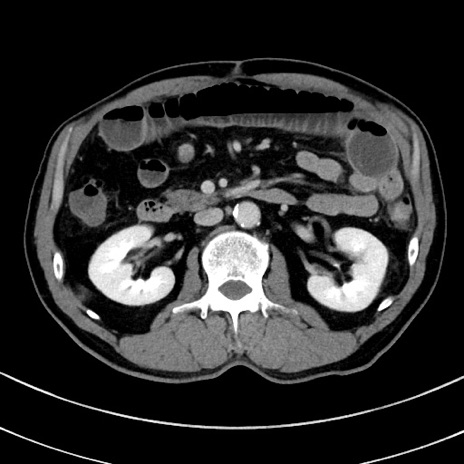

症例8(横断像)

【症例】 60歳代男性

【主訴】 黒色吐物

【現病歴】 4日前から嘔気自覚、2日前の朝食後にも嘔気あり、自分で手で嘔吐反射起こし嘔吐したところ血が混ざっていたため受診。

【既往歴】 5年前汎発性腹膜炎を伴う急性虫垂炎で手術、高血圧、前立腺肥大症、高脂血症

【身体所見】 腹部正中に手術癩痕あり 腹部平坦・軟圧痛なし膨満感あり

【データ】WBC 8400、CRP 4.54